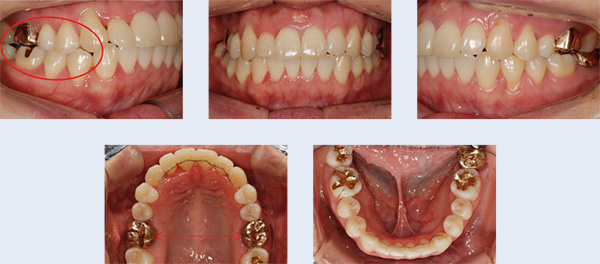

고르지 않은 앞니의 교정 치료를 위해 내원한 26세 여성입니다. 상대적으로 위턱의 공간이 아래턱에 비해 좁아 비대칭이 나타난 상황이었으나, 이를 빼거나 양악수술을 원치 않으셔서 그 대안으로 위턱뼈의 공간 확장 (MARPE)과 미니스크류를 이용하여 아래 치아를 후방 이동시킨 후 공간을 확보하는 치료 계획으로 진행되었습니다.

① 위턱의 골격적 확장을 위해 미니스크류를 이용한 급속구개확장장치(MARPE) 적용

② 교정용 미니스크류(miniscrew) 식립 및 사랑니가 있던 공간으로 어금니 후방 이동

발치와 양악수술 없이 자연스럽고 고른 치열을 갖게 되어 앞니의 심미적인 개선을 기대한 환자 분의 만족감이 높았습니다.